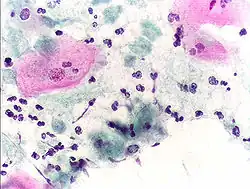

Micrograph of a Pap test showing a low-grade intraepithelial lesion (LSIL) and benign endocervical mucosa. Pap stain. -